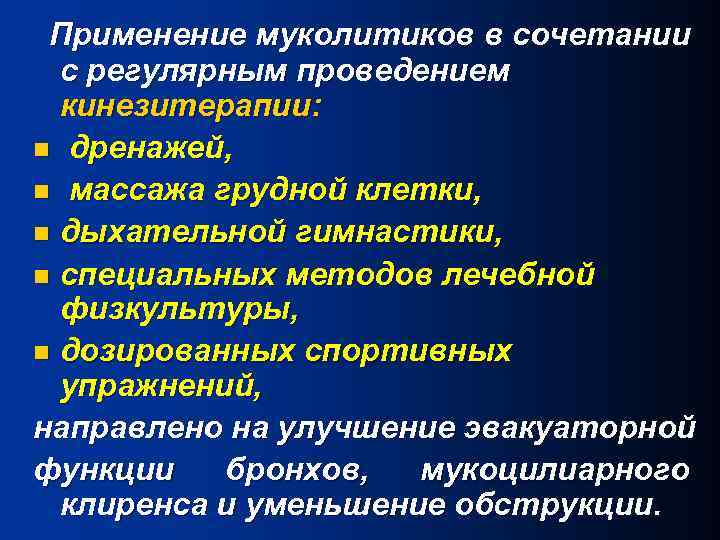

Применение муколитиков в сочетании с регулярным проведением кинезитерапии: n дренажей, n массажа грудной клетки, n дыхательной гимнастики, n специальных методов лечебной физкультуры, n дозированных спортивных упражнений, направлено на улучшение эвакуаторной функции бронхов, мукоцилиарного клиренса и уменьшение обструкции.